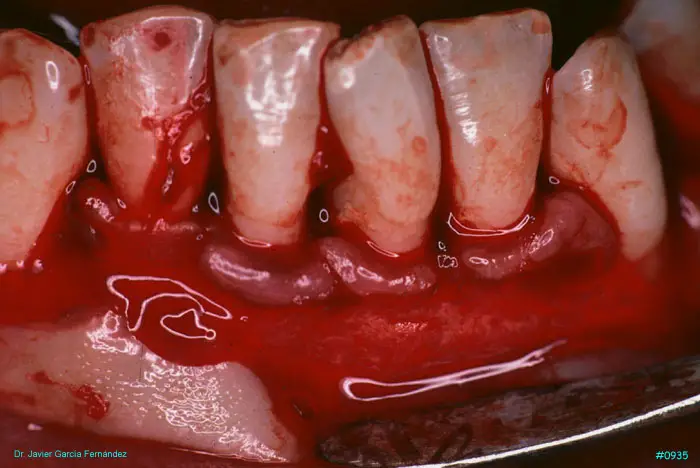

Atlas of Surgical Techniques in Periodontics. Chapter III. Atlas de Técnicas Quirúrgicas en Periodoncia

image310